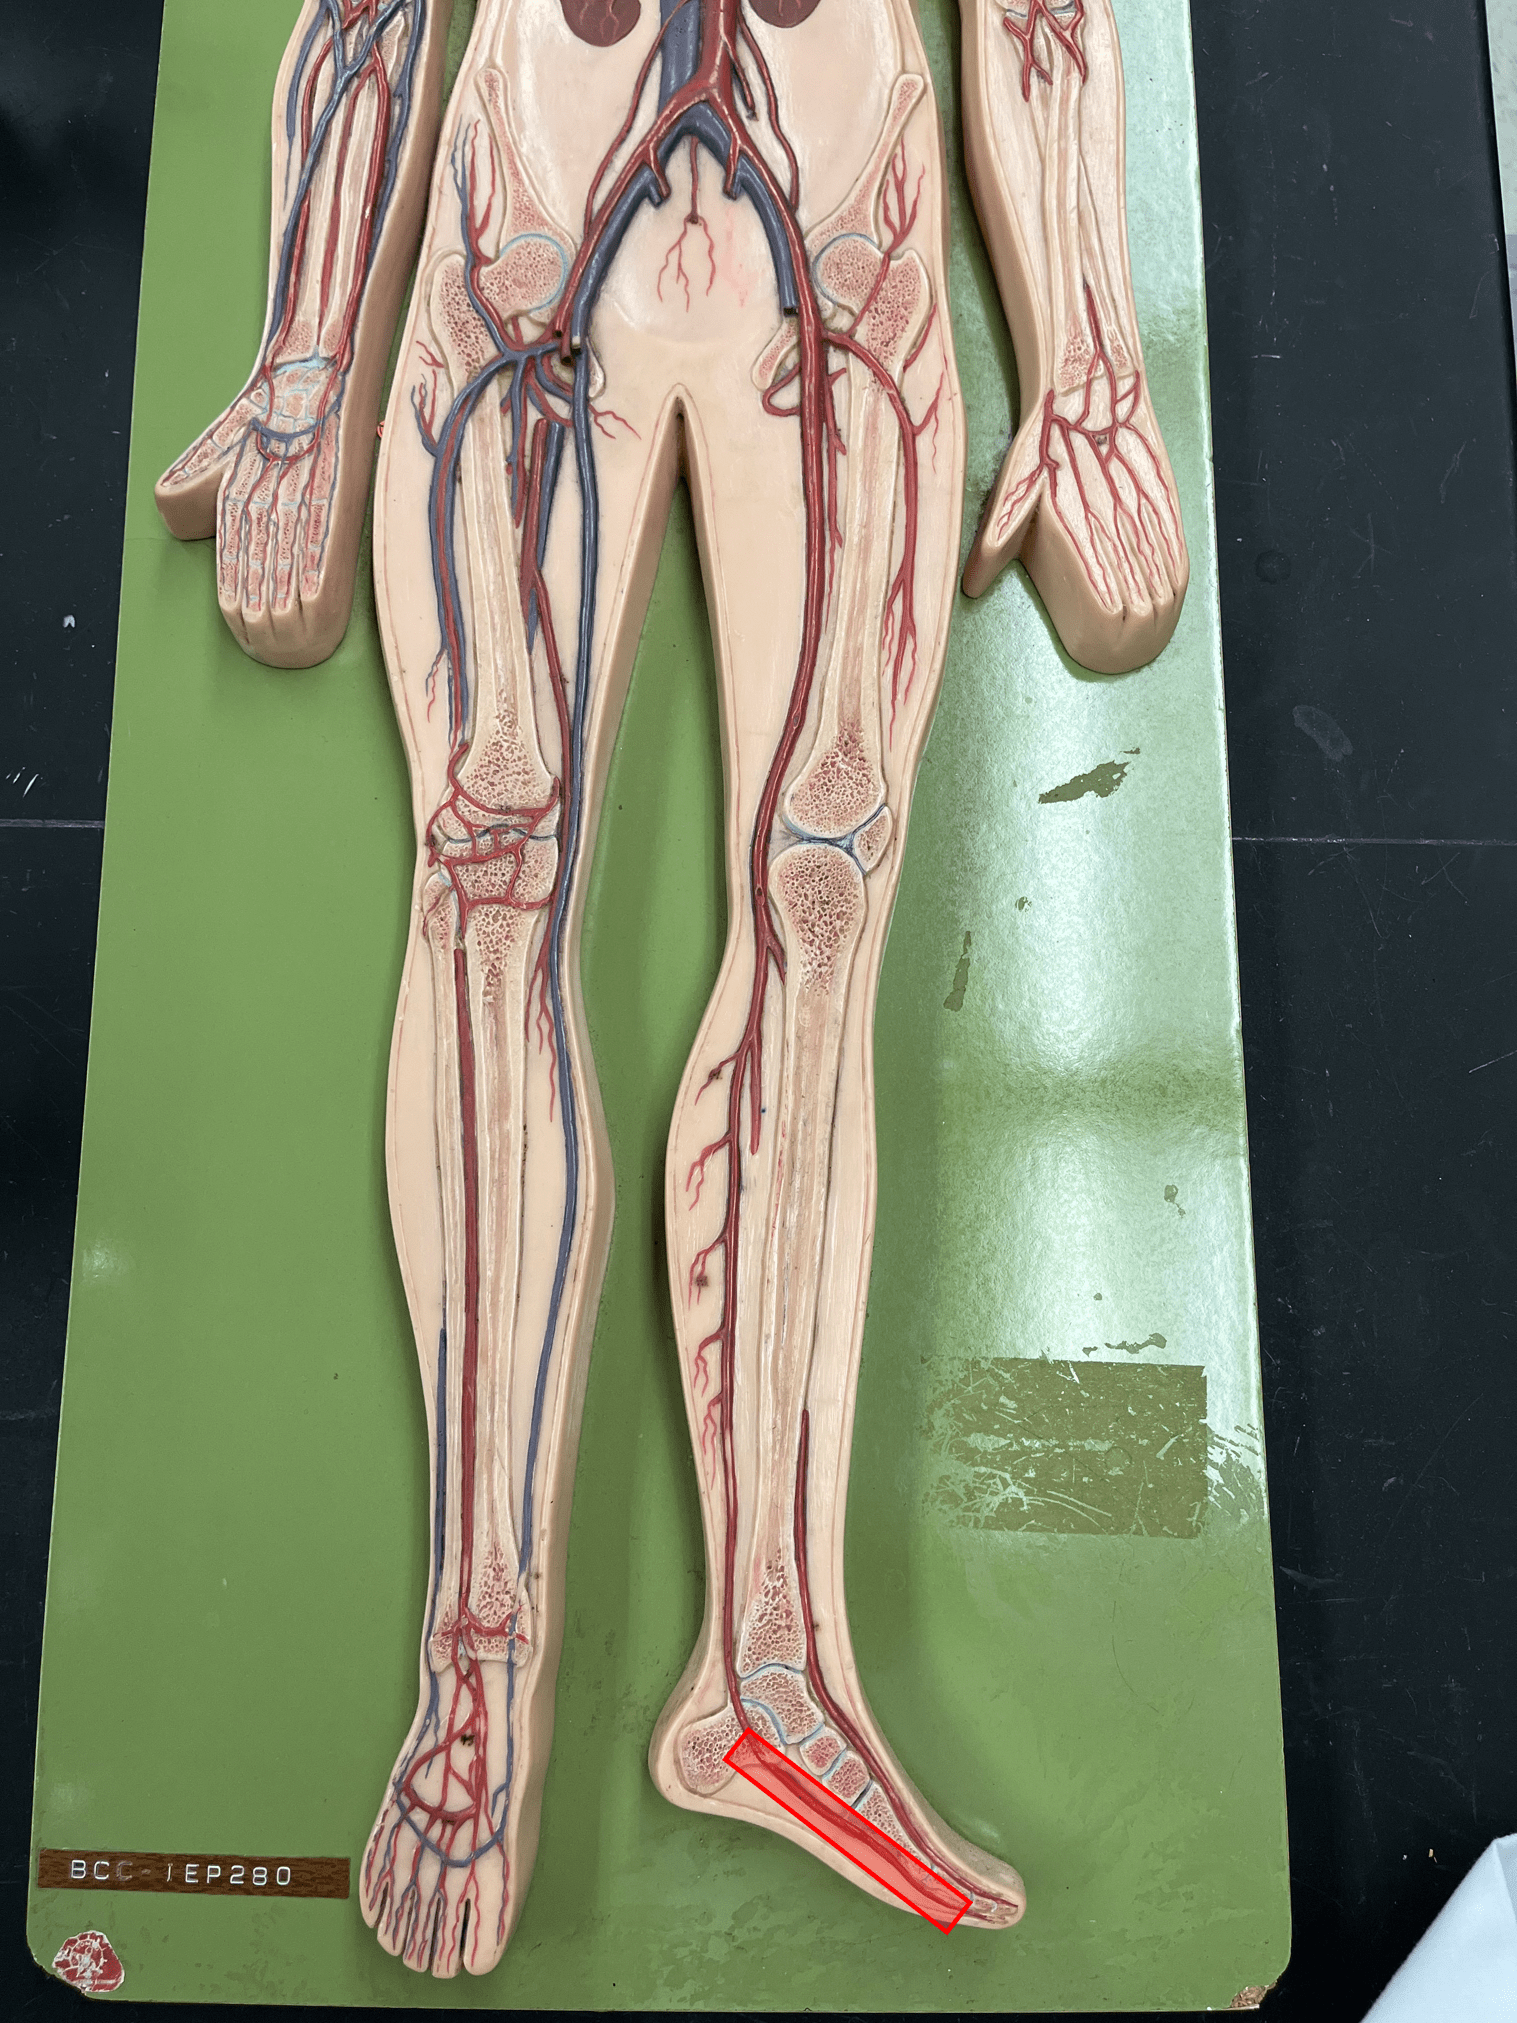

• Composes a smooth inner surface of the vessel.

12

valve

• Found in some veins.